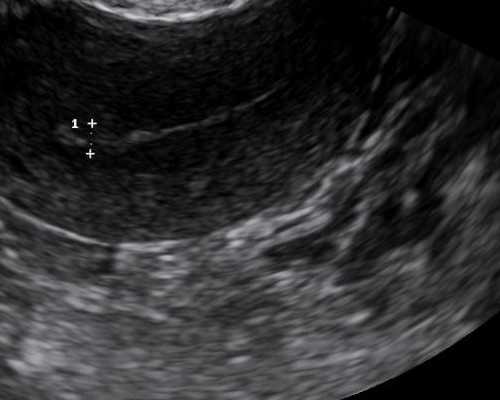

为了顺利怀上健康的宝宝,黄女士和她的丈夫选择了国际先进的技术,即植入前胚胎基因筛查。经诱导排卵、ICSI受精、胚胎培养,最终获得5个优质胚泡。经过遗传室技术人员检测,三个胚胎的基因组完全正常。经与家属充分讨论,胚胎成功移植到黄女士子宫内,顺利受孕。

整个孕期,黄女士和胎儿一路走过。特别是胎儿在孕18周经羊膜穿刺术确诊为正常后,于2015年2月2日,孕37周,孕3天剖腹产出一名健康男婴,体重3400克,各项身体指标均正常。